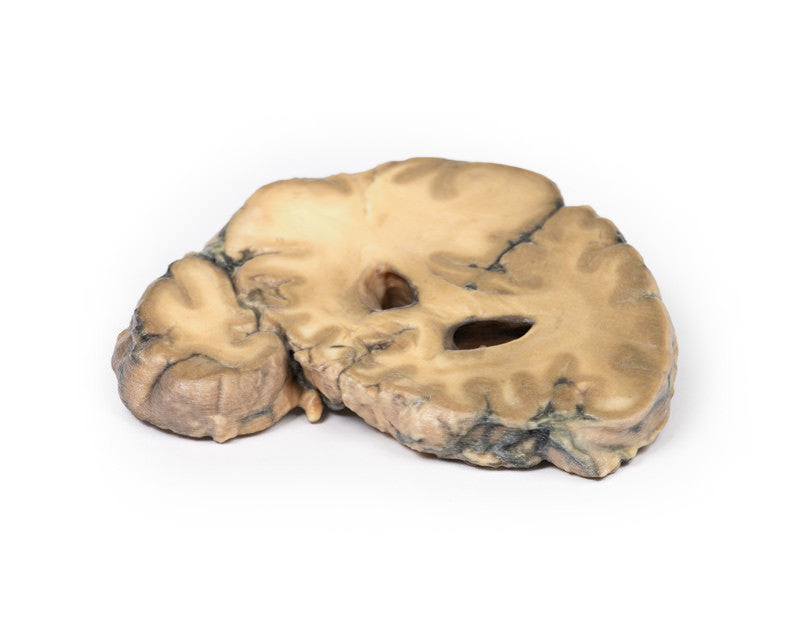

This brain specimen is cut in the coronal plane. A circumscribed, variegated, pink-grey tumour is evident in the right frontal lobe. The tumour is involving the grey and white matter. Compression of the right lateral ventricle by the lesion is apparent with shift of the midline structures also seen.